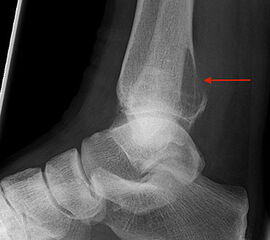

Die beiden häufigsten primären malignen Knochentumoren überhaupt, das Osteosarkom und Chondrosarkom, finden sich neben dem Ewing-Sarkom auch im Bereich des Fußes am häufigsten. Diese Tumoren können sich klinisch wie auch bildgebend sehr variabel darstellen, was die hohe Anzahl von Fehldiagnosen und verzögerten Diagnosestellungen erklären kann 25. Osteosarkome treten im Bereich des Fußes im Vergleich zu den typischen Lokalisationen (kniegelenksnah) durchschnittlich ca. 10 Jahre später auf (Abb. 15). Der Calcaneus ist die bevorzugte Lokalisation für Osteosarkome des Fußskeletts und ein Großteil dieser Tumoren ist schlecht differenziert (G3) 46. Das Verteilungsmuster des Ewing-Sarkoms ist noch heterogener. In einer Nachuntersuchung von 1997 zeigten sich 6 von 16 Ewing-Sarkomen im Bereich der Metatarsalia, 4 in den Phalangen, 3 im Calcaneus und jeweils eines im Talus und eines im Os navikulare 47. Das durchschnittliche Patientenalter unterscheidet sich nicht von den herkömmlichen Lokalisationen. Auffällig ist jedoch die erhebliche Diagnoseverzögerung. So vergehen bei einem Ewing-Sarkom-Befall des Fußes durchschnittlich 14 Monate von Beginn der Symptome bis zur korrekten Diagnosestellung, bei Lokalisation im Rückfuß sind es gar 22 Monate (Abb. 28). Die Therapie des Ewing- und Osteosarkoms des Fußes unterschei­det sich grundsätzlich nicht von der etablierten Behandlungsstrategie dieser Tumoren und umfasst in der Regel die neo-adjuvante Chemotherapie, weite Tumorresektion und anschließende adjuvante Chemotherapie. Die Strahlentherapie besitzt in der Behandlung des Ewing-Sarkoms unverändert einen hohen Stellenwert. Ewingsarkome sind definitions­gemäß stets schlecht differenziert (G3 bzw. G4), also hoch maligne. Das operative Vorgehen ist dieser Tatsache anzupassen.

Metastasen finden sich in den distalen Abschnitten der Extremitäten deutlich seltener als in den proximalen (Abb.29 und 30). Am Fuß sind Metastasen somit vergleichsweise selten anzutreffen (<1%). Lungenkarzinome stellen hierbei den häufigsten Primärtumor dar 48 (Abb.31).